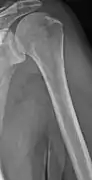

The diagnostic examination of a person with suspected multiple myeloma typically includes a skeletal survey. This is a series of X-rays of the skull, axial skeleton, and proximal long bones. Myeloma activity sometimes appears as "lytic lesions" (with local disappearance of normal bone due to resorption). And on the skull X-ray as "punched-out lesions" (pepper-pot skull). Lesions may also be sclerotic, which is seen as radiodense.[47] Overall, the radiodensity of myeloma is between −30 and 120 Hounsfield units (HU).[48] Magnetic resonance imaging is more sensitive than simple X-rays in the detection of lytic lesions, and may supersede a skeletal survey, especially when vertebral disease is suspected. Occasionally, a CT scan is performed to measure the size of soft-tissue plasmacytomas. Bone scans are typically not of any additional value in the workup of people with myeloma (no new bone formation; lytic lesions not well visualized on bone scan).

Multiple myeloma in the upper arm

Femur with multiple myeloma lesions

Humerus with multiple myeloma lesions